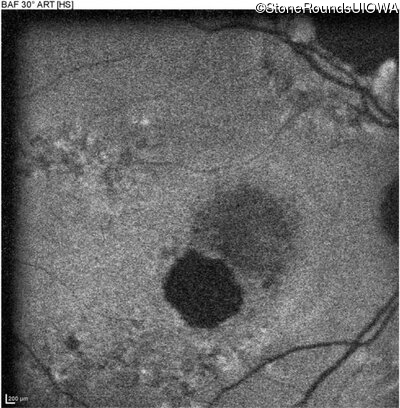

Blue Autofluorescence - Right - 20/125 -2

Exemplar